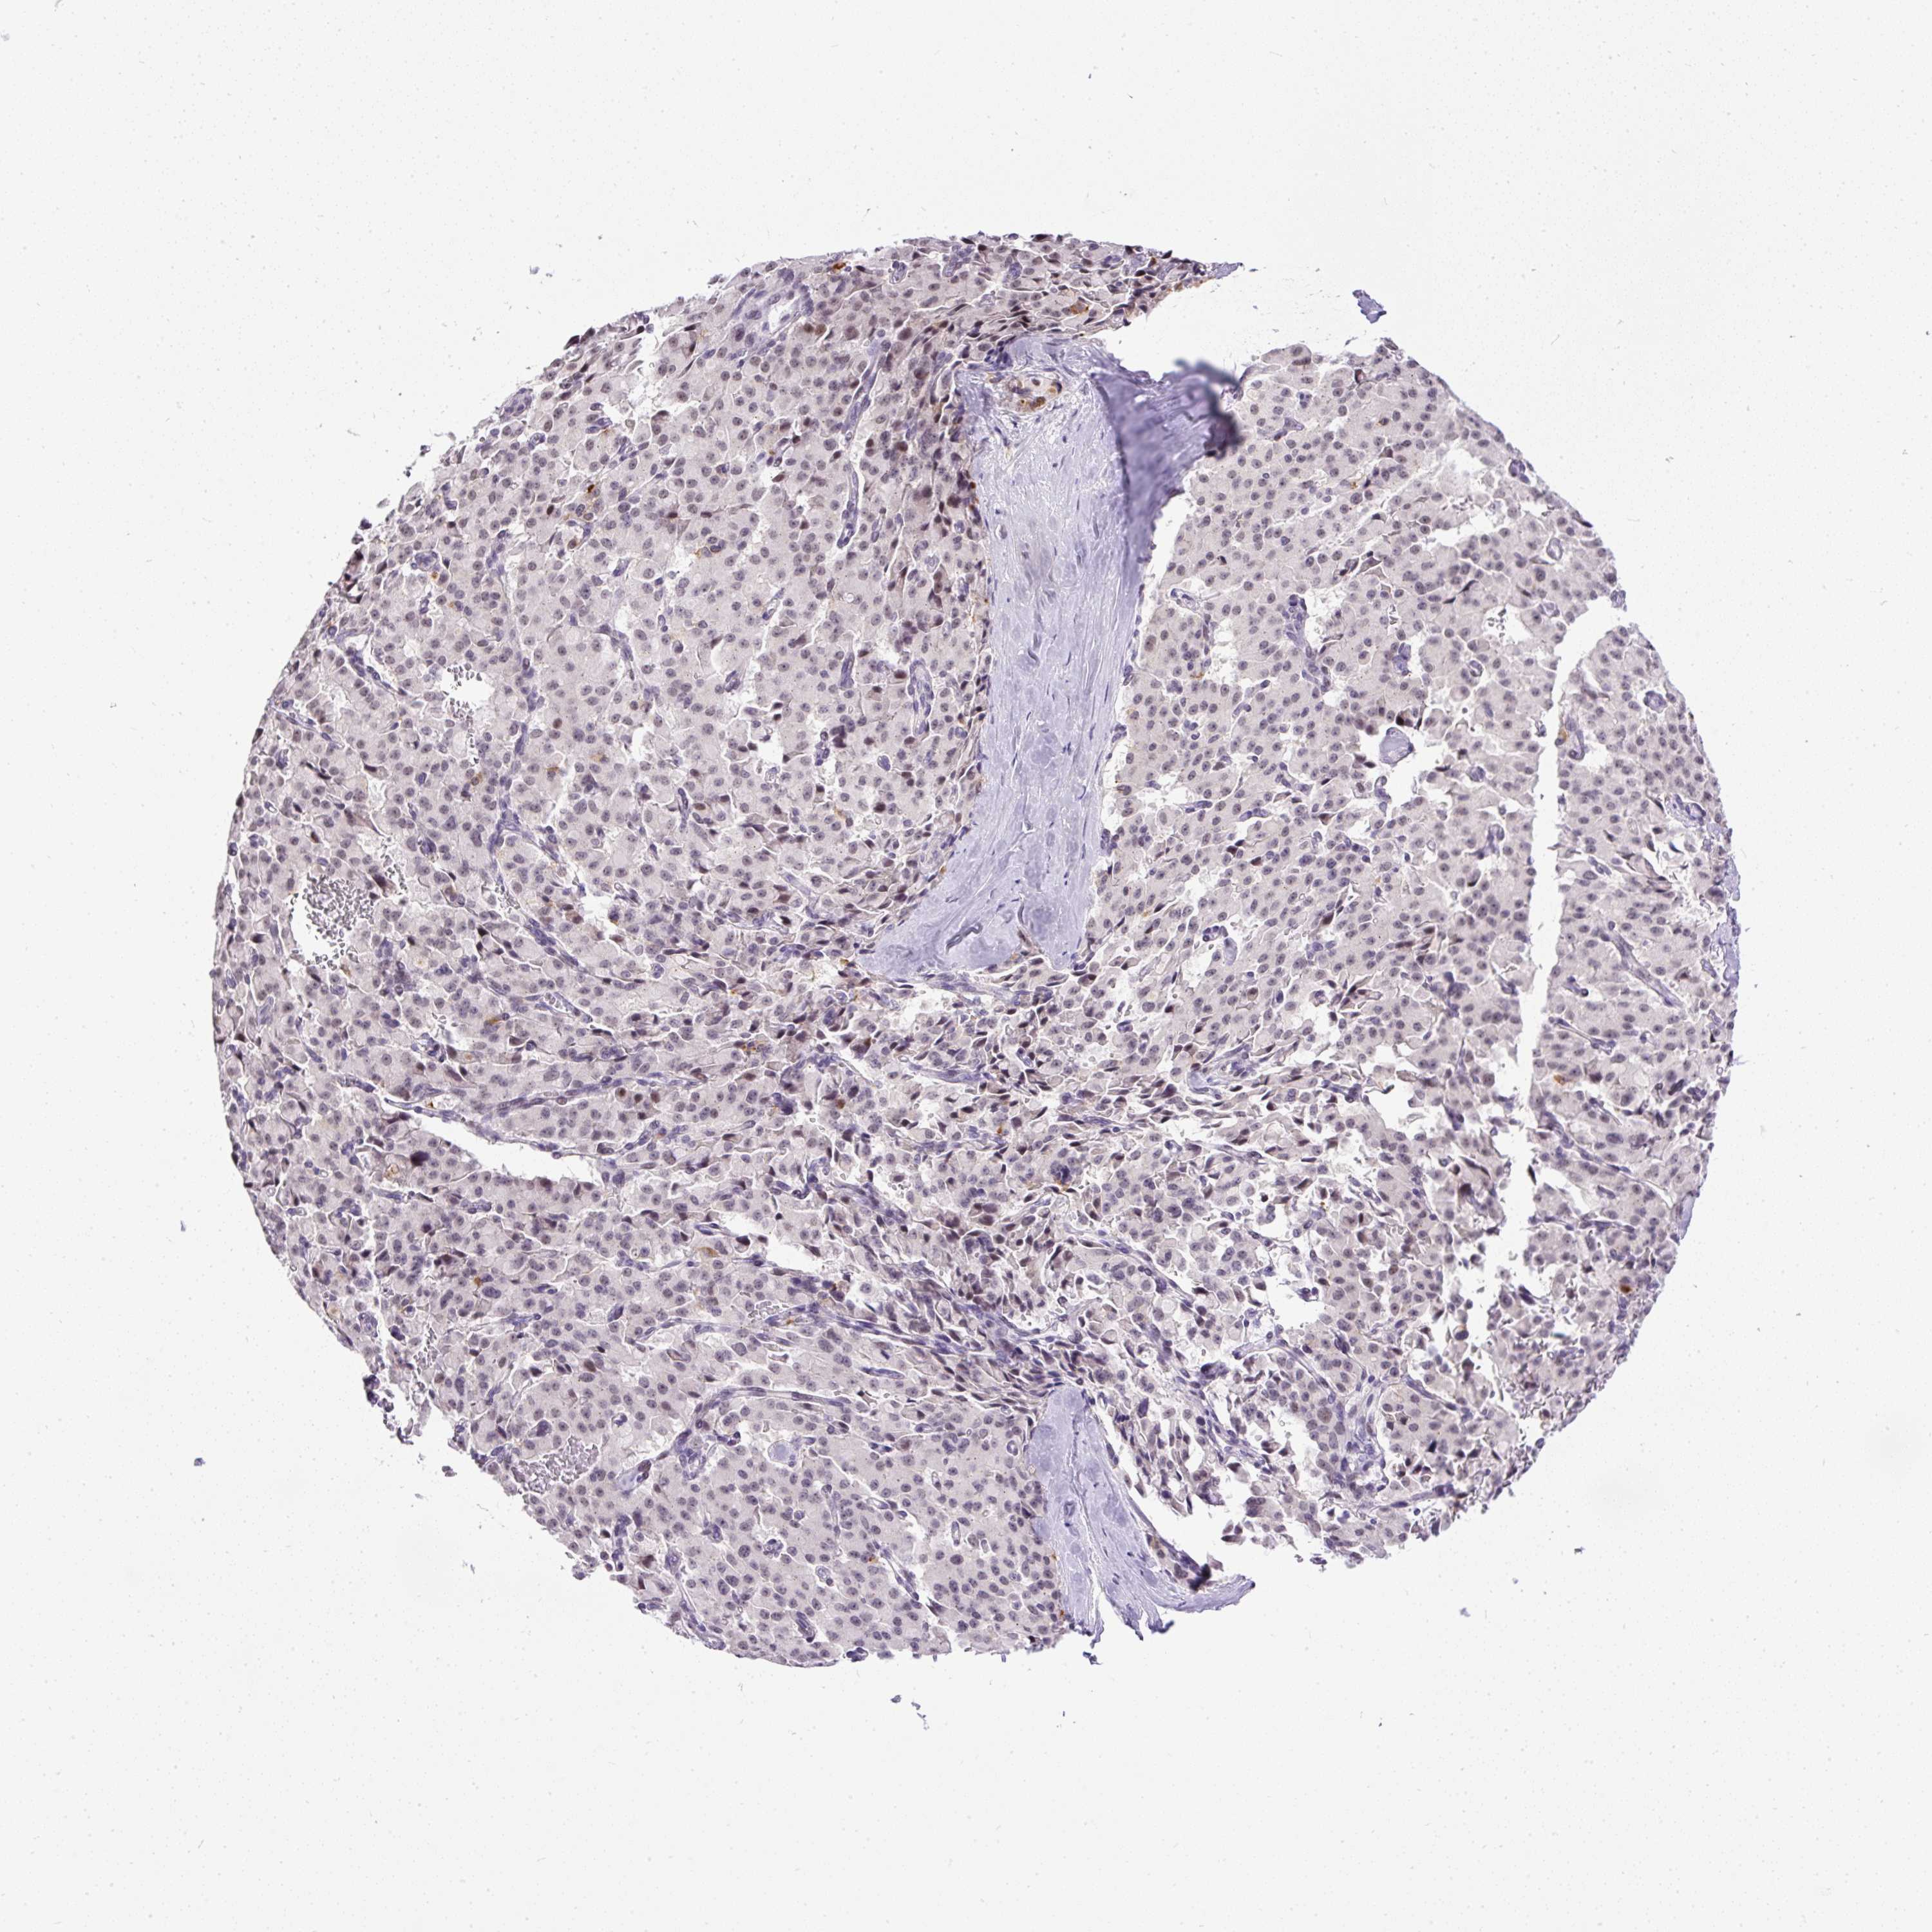

PANCREATIC CANCER - Protein expressioni

A mouse-over function shows sample information and annotation data. Click on an image to view it in a full screen mode. Samples can be filtered based on level of antibody staining by selecting one or several of the following categories: high, medium, low and not detected. The assay and annotation is described here.

Note that samples used for immunohistochemistry by the Human Protein Atlas do not correspond to samples in the TCGA dataset.

Antibody stainingi

Antibody staining in the annotated cell types in the current human tissue is reported as not detected, low, medium, or high, based on conventional immunohistochemistry profiling in selected tissues. This score is based on the combination of the staining intensity and fraction of stained cells.

Each image is clickable and will lead to virtual microscopy that enables deeper exploration of all samples and also displays staining intensity scores, fraction scores and subcellular localization as well as patient and tissue information for each sample.

Antibody HPA055048

Staining

High

Medium

Low

Not detected

Intensity

Strong

Moderate

Weak

Negative

Quantity

>75%

75%-25%

<25%

None

Location

Nuclear

Cytoplasmic/membranous

Cytoplasmic/membranous,nuclear

Adenocarcinoma, NOS